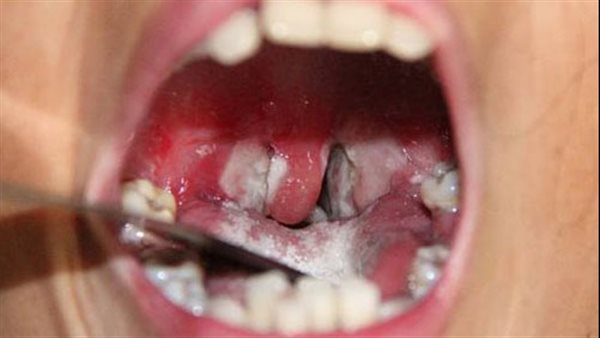

وأشارت منظمة الصحة العالمية، إلى أن مرض الدفتيريا الذي تسببه بكتيريا تسمى Corynebacterium diphtheriae، ويحدث عندما تطلق سمومًا تسبب تراكم الأنسجة الرمادية في الحلق، مما يسبب مشاكل خطيرة في البلع والتنفس، وذلك في المناطق الأكثر دفئًا، كمل يصاب المصابون بالدفتيريا أحيانًا بقرح جلدية لا تلتئم وتصبح مغطاة بأنسجة رمادية، حيث يحدث هذا النوع من الدفتيريا، والمعروف باسم الدفتيريا الجلدية في الولايات المتحدة.